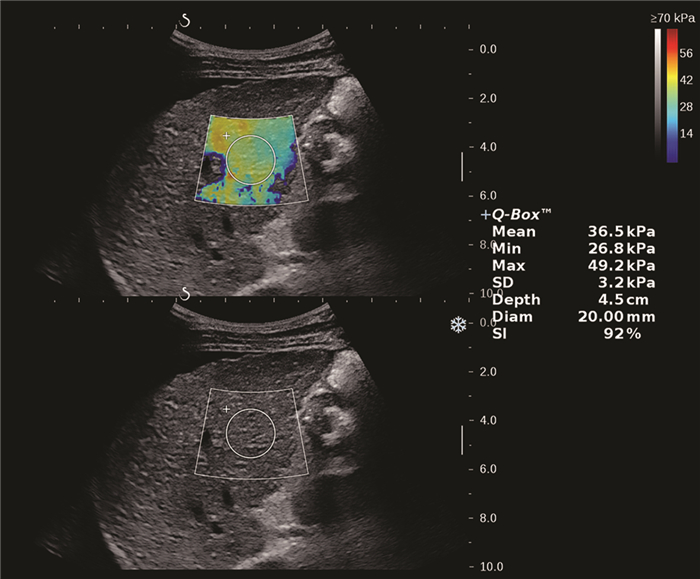

Clinical value of two-dimensional shear wave elastography in predicting esophageal varices in patients with hepatitis B cirrhosis by evaluating liver and spleen stiffness

Xuemei WANG, Yao ZHANG, Xueping YANG, Yue WANG, Mixue WANG

2021, 37(5): 1081-1084. DOI: 10.3969/j.issn.1001-5256.2021.05.021

Abstract(1416) HTML (293) PDF (2305KB)(79)

Abstract:

Objective  To investigate the value of two-dimensional shear wave elastography (2D-SWE) in the noninvasive evaluation of the presence or absence of esophageal varices (EV) in patients with hepatitis B cirrhosis by liver stiffness measurement (LSM) and spleen stiffness measurement (SSM).  Methods  A total of 172 patients who were diagnosed with hepatitis B cirrhosis in Beijing Ditan Hospital, Capital Medical University, from April 2019 to February 2020 were enrolled in a prospective study, and according to the results of gastroscopy, they were divided into non-EV group and EV group. The two groups were compared in terms of spleen thickness (ST), spleen diameter (SD), LSM, and SSM. The independent samples t-test was used for comparison of normally distributed continuous data between two groups, and the Mann-Whitney U test was used for comparison of non-normally distributed continuous data between two groups; the chi-square test was used for comparison of categorical data. The receiver operating characteristic (ROC) curve was used to investigate the value of LSM and SSM in the diagnosis of EV, and the Z test was used to compare the diagnostic accuracy of LSM and SSM.  Results  There were 121 patients in the EV group and 51 patients in the non-EV group. There were significant differences between the two groups in ST (t=8.143, P < 0.001), SD (t=7.363, P < 0.001), LSM (Z=3.024, P=0.002), SSM (t=15.142, P < 0.001), and presence or absence of ascites (χ2=22.101, P < 0.001). LSM had an area under the ROC curve (AUC) of 0.646 (95% confidence interval [CI]: 0.570-0.718) in the diagnosis of EV, with a sensitivity (Se) of 83.47%, a specificity (Sp) of 47.06%, a positive predictive value (PPV) of 78.9%, and a negative predictive value (NPV) of 54.5% at the optimal cut-off value of 13.16. SSM had an AUC of 0.951 (95% CI: 0.907-0.978) in the diagnosis of EV, with an Se of 80.99%, an Sp of 96.08%, a PPV of 98.0%, and an NPV of 68.1% at the optimal cut-off value of 38.08. SSM had a better diagnostic accuracy than LSM (Z=6.096, P < 0.001).  Conclusion  LSM and SSM can be used to predict the presence or absence of EV in patients with hepatitis B cirrhosis. SSM has a higher accuracy than LSM and can provide accurate diagnostic information for clinical practice.